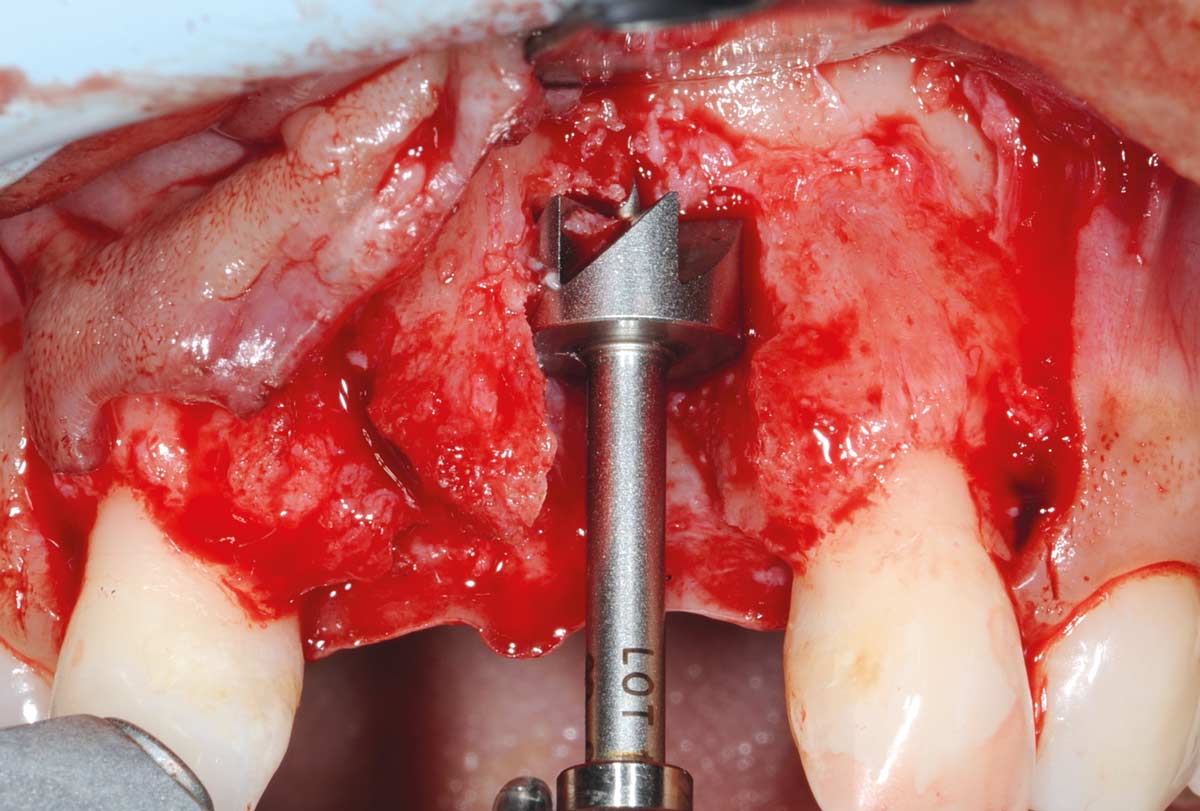

4/26 - Determine the defect size with the trephineBone augmentation in aesthetic zone with maxgraft® bonering - Dr. A. Patel